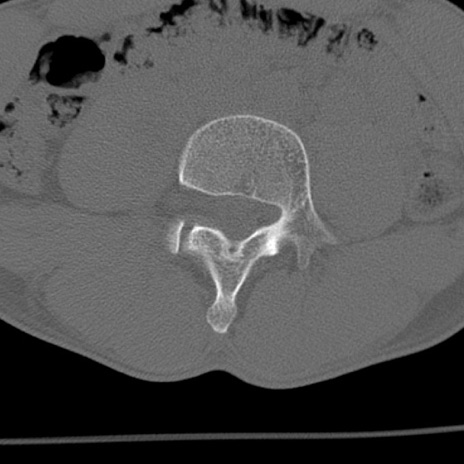

症例3 腰椎CT(横断像)

腰椎CT